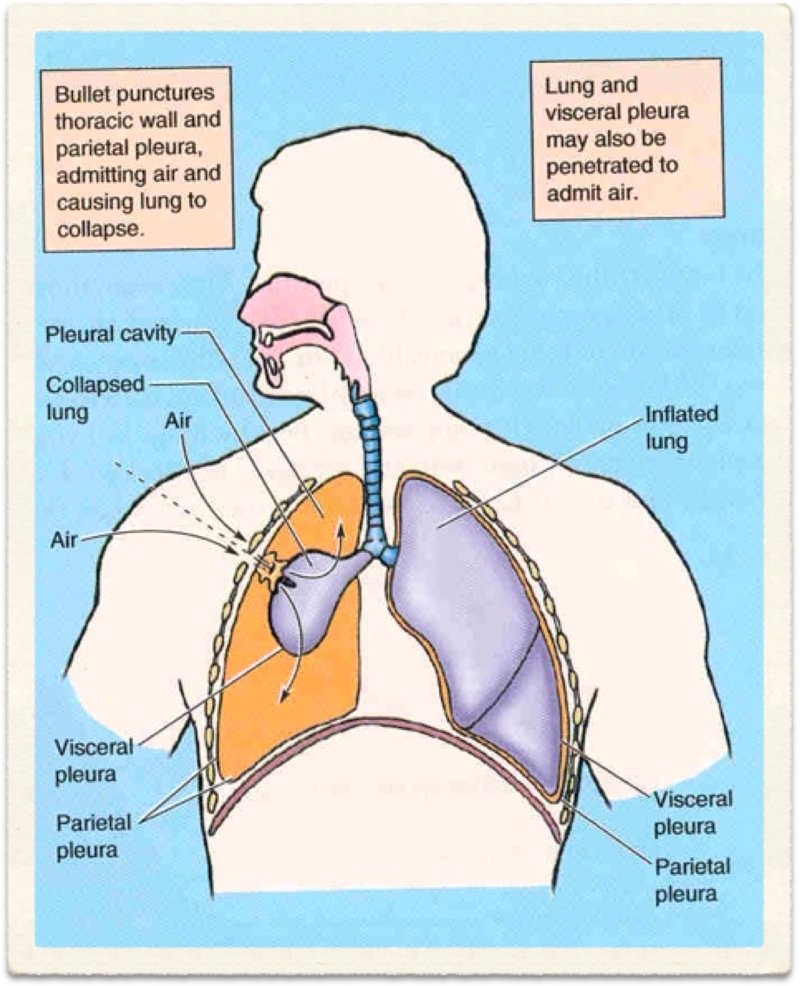

Chronic Obstructive Pulmonary Disease (COPD) is an 'umbrella' term for people with chronic bronchitis, emphysema, or both. With COPD the airflow to the lungs is restricted (obstructed). COPD is usually caused by smoking. Symptoms include cough and breathlessness.